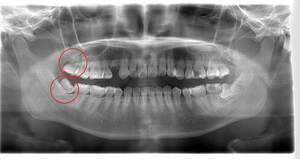

できれば痛くなく抜きたい症例

- 抜歯前写真(レントゲン)

| 年齢 | 20代・女性 |

|---|---|

| 主訴 | 左下親知らずがたまに痛み、できれば痛くなく抜きたい |

| 親知らずの生え方 | 完全に埋まっている、横向きに生えている |

| 抜歯時間 | 50分 |

| 費用 | 約8,000円(保険診療、CT代含む) |

| 抜歯内容 | 左下親知らずが横向きになって半分埋まっている状態だったため、麻酔を行い、親知らずの奥の歯ぐきに切開をいれ、歯が囲んでいる骨を削り、歯の頭の部分を削って出し、その後根の部分に器具をかけて抜歯しました。 親知らずが一部神経に近い部分があったため、術後に麻痺が出る可能性がありました。このケースでは事前にCTを撮影し、歯の位置、根の方向、神経との距離を確認していたため、幸い麻痺が出ることはありませんでした。 術後1週間経過して糸取りをして治療は終了となりました。抜歯後3日間は腫れと痛みで大変だったが、糸取りをする頃には痛みも腫れも無くなったと患者さまも喜んでおられました。 |